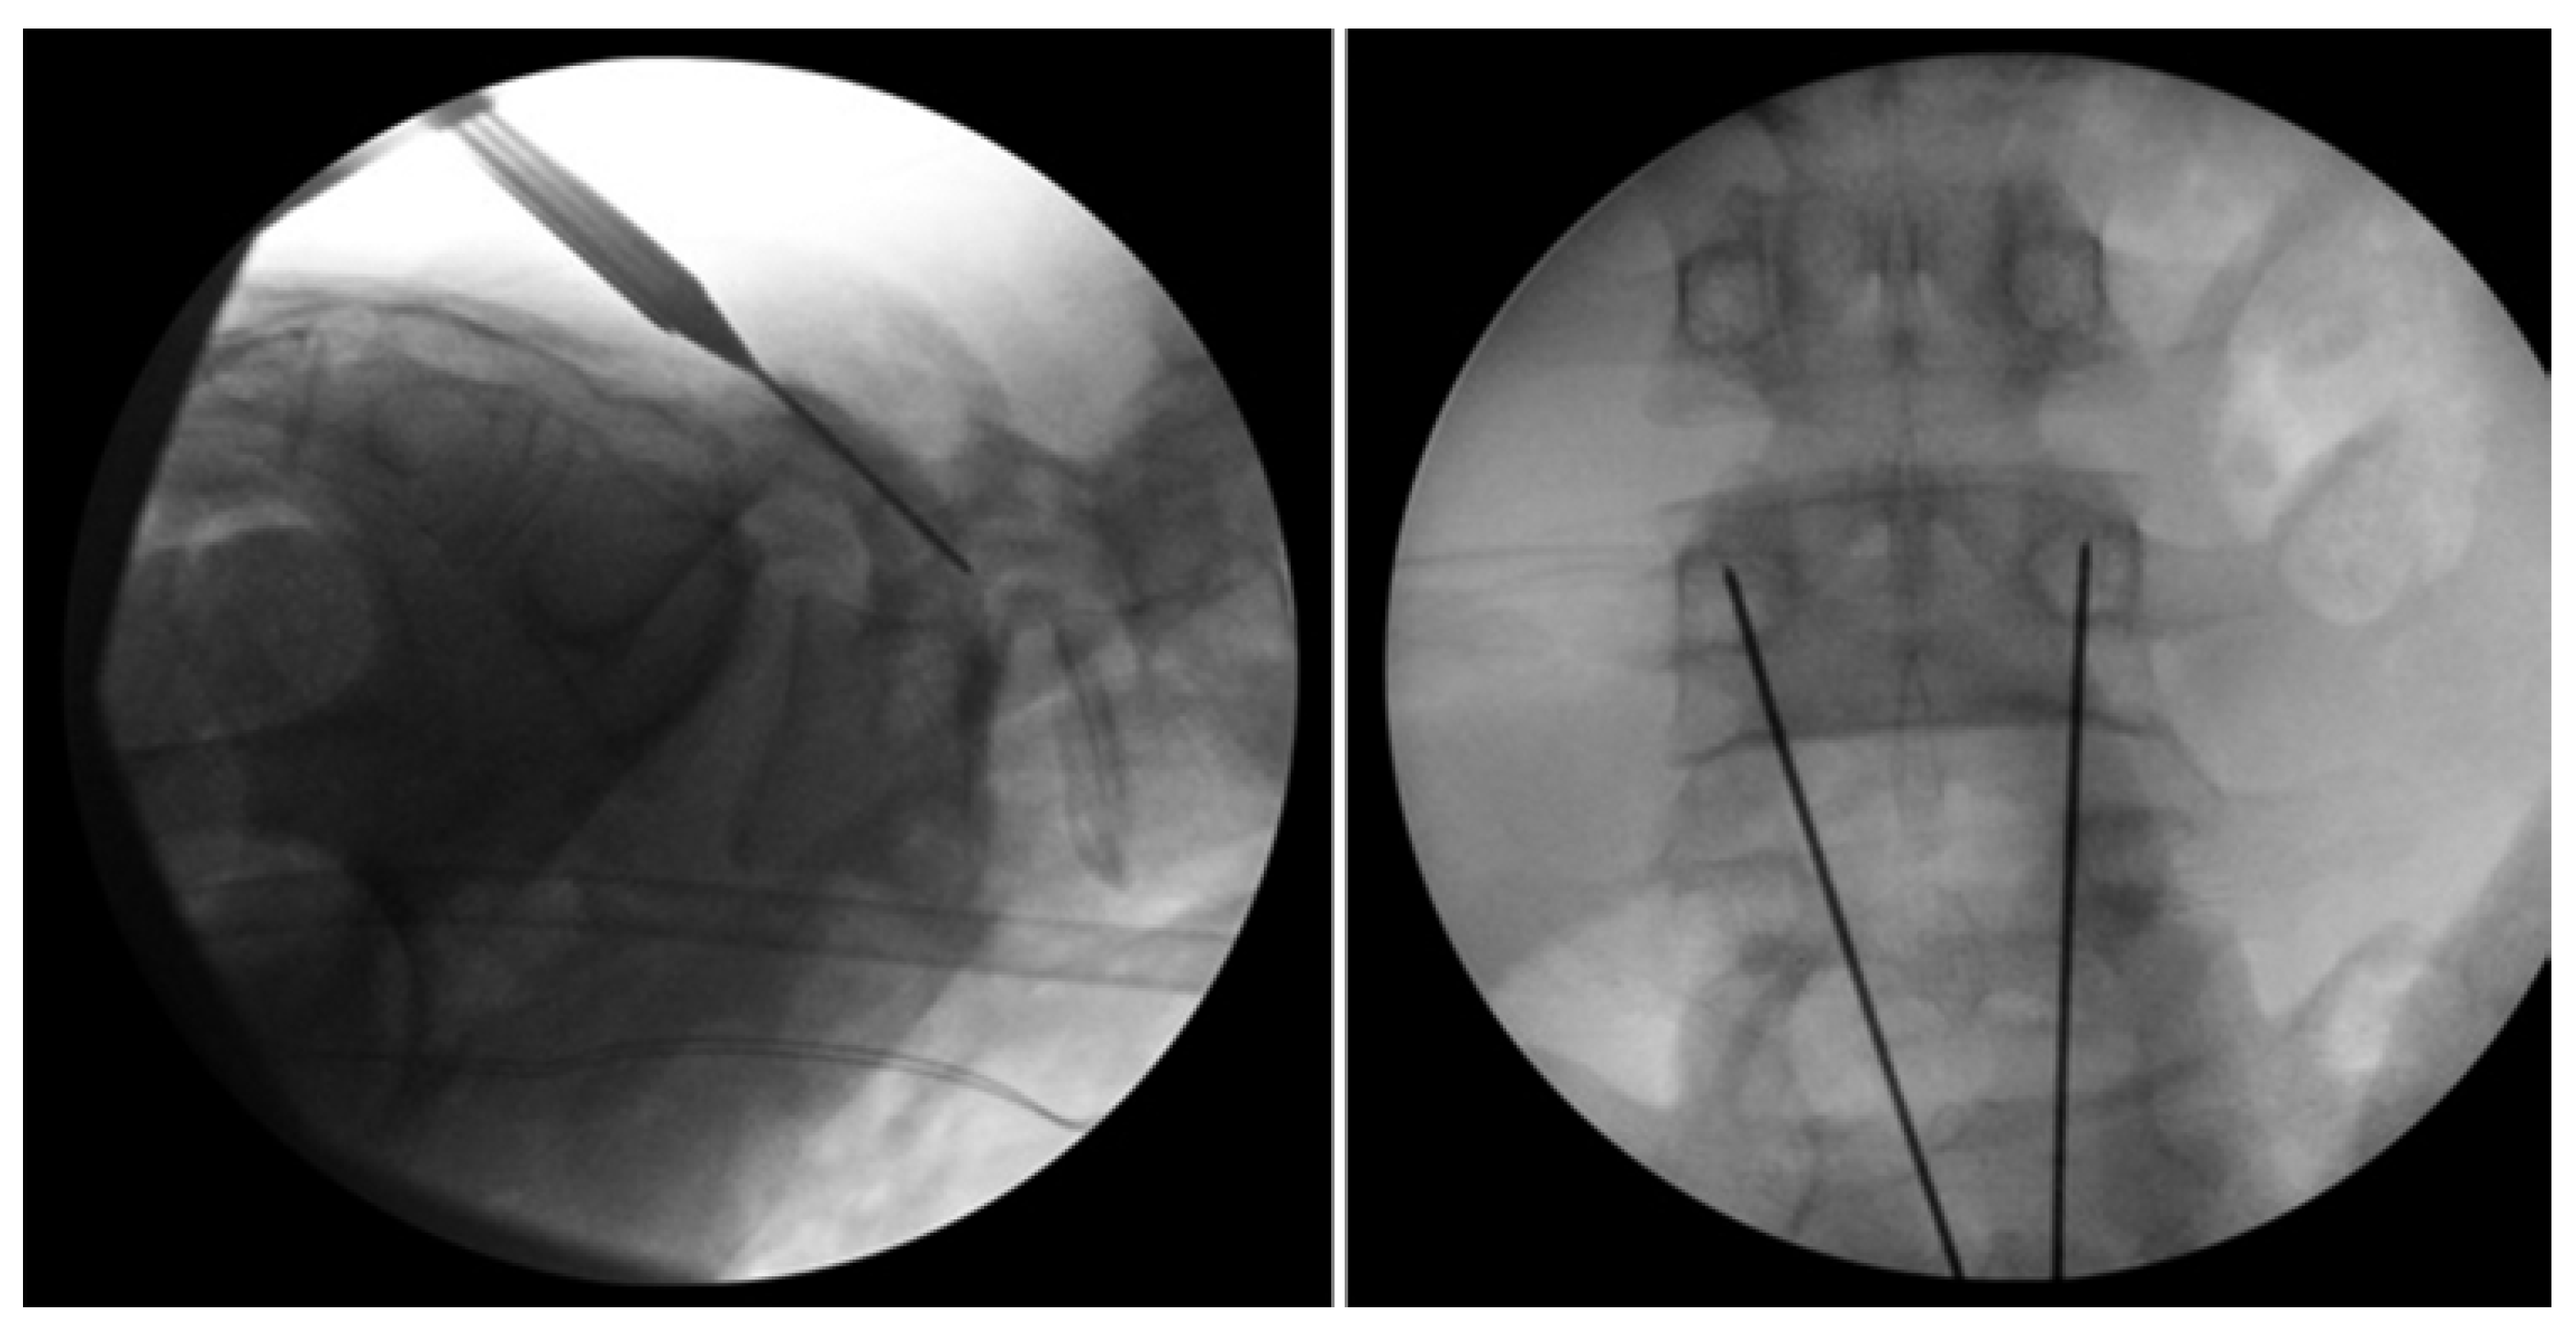

Levi Technique—Minimally Invasive Direct Pars Screw Placement

- Fayed, I.; Conte, A.G.; Voyadzis, J.-M. Success and failure of percutaneous minimally invasive direct pars repair: Analysis of fracture morphology. World Neurosurg. 2019, 126, 181–188. [Google Scholar] [CrossRef]

- Widi, G.A.; Williams, S.K.; Levi, A.D. Minimally invasive direct repair of bilateral lumbar spine pars defects in athletes. Case Rep. Med. 2013, 2013, 659078. [Google Scholar] [CrossRef]

- Ghobrial, G.M.; Crandall, K.M.; Lau, A.; Williams, S.K.; Levi, A.D. Minimally invasive direct pars repair with cannulated screws and recombinant human bone morphogenetic protein: Case series and review of the literature. Neurosurg. Focus 2017, 43, E6. [Google Scholar] [CrossRef] [PubMed]